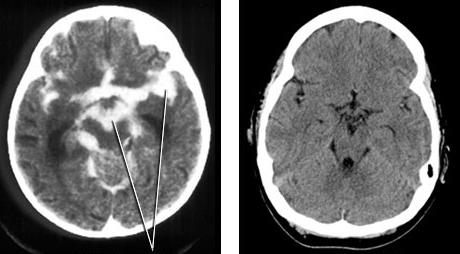

Po fazie zwiastunowej zwykle wielu ludzi dochodzi do siebie, objawy mijają i bez przeszkód można wrócić do wszystkich obowiązków. Wiele osób nie zdaje sobie właściwie sprawy z faktu, że przeszło chorobę. Jeżeli choroba nie ustaje, a wręcz się nasila i chory zostaje hospitalizowany, to jednoznacznie jest to znak, że schorzenie przeszło w fazę objawową. Faza ta zwykle charakteryzuje się zapaleniem opon mózgowych lub mózgu. Chory uskarża się na dreszcze, bardzo wysoką gorączkę, dochodzącą nawet do 41 stopni, omamy, nierzadko też następuje utrata przytomności. Pojawiają się także duszności i problemy z oddychaniem. Faza objawowa leczona jest tylko i wyłącznie poprzez hospitalizację chorego. W fazie tej można zaobserwować również sztywnienie karku, oczopląs, bardzo często dochodzi także do porażenia nerwów np. twarzy, czy ciała, ponieważ choroba ta ma niezwykle charakterystyczne objawy. Kleszczowe zapalenie opon mózgowych może prowadzić także do ciężkich niedowładów, zdarza się to stosunkowo rzadko, jednak gdy choroba wejdzie w stadium zaawansowania, może dojść nawet do trwałej niepełnosprawności. Chory nie odzyska uczucia w poszczególnych partiach ciała.

W ciężkich przypadkach faza ta może doprowadzić do śpiączki pacjenta, a nawet do śmierci, dlatego trzeba zachować szczególną ostrożność i poddać się niezwłocznie leczeniu. Najrzadszym objawem tej choroby jest zapalenie rdzenia kręgowego, kończy się ono ciężkim niedowładem, a nawet niepełnosprawnością. Brak możliwości poruszania kończynami czy zaburzenia czucia rozwijają się w tej fazie niezwykle szybko, leczenie to wielomiesięczna hospitalizacja, połączona z rehabilitacją. Przy zapaleniu opon mózgowych faza objawowa trwa do 2 tygodni, niestety przy zapaleniu rdzenia kręgowego leczenie może wydłużyć się nawet do 2 miesięcy.

Co jest istotne, odkleszczowe zapalenie mózgu jest chorobą, która atakuje układ nerwowy człowieka. Po pierwszych symptomach nie da się jednak jednoznacznie rozpoznać tej choroby. Jeśli natomiast wirus atakuje nerwy wewnątrzczaszkowe, pacjent najczęściej zapada na zapalenie opon mózgowych lub zapalenie mózgu. Choroba ta również może zaatakować kręgosłup i rdzeń. Niestety, trzeba zwracać szczególną uwagę na choroby, które przyczyniają się do wadliwego funkcjonowania układu nerwowego, ponieważ może się to skończyć trwałą niepełnosprawnością. Odkleszczowe zapalenie mózgu może spowodować porażenie mięśni twarzy, kończyn lub poszczególnych partii na ciele, niestety, nie zawsze porażenia te są odwracalne. Bardzo często zaatakowanie nerwu skutkuje trwałym niedowładem. Chory poddawany jest oczywiście rehabilitacji, która ma dosyć dobre rezultaty. Wiele osób całkowicie lub częściowo odzyskuje sprawność fizyczną, a niekiedy objawy te całkowicie mijają. Pierwszymi, znaczącymi symptomami, świadczącymi o zaatakowaniu nerwów przez odkleszczowe zapalenie mózgu są dreszcze oraz drętwienia, nie wolno lekceważyć tych objawów i należy niezwłocznie zgłosić się do lekarza. Wiele osób uskarża się także na sztywnienie karku oraz niemożność poruszania szyją, są to typowe objawy KZM, świadczące o zaatakowaniu układu nerwowego. Natychmiastowe leczenie oraz rehabilitacja są w stanie zapobiec rozwojowi choroby, powikłaniom, a także niechcianym niezwykle negatywnym skutkom.